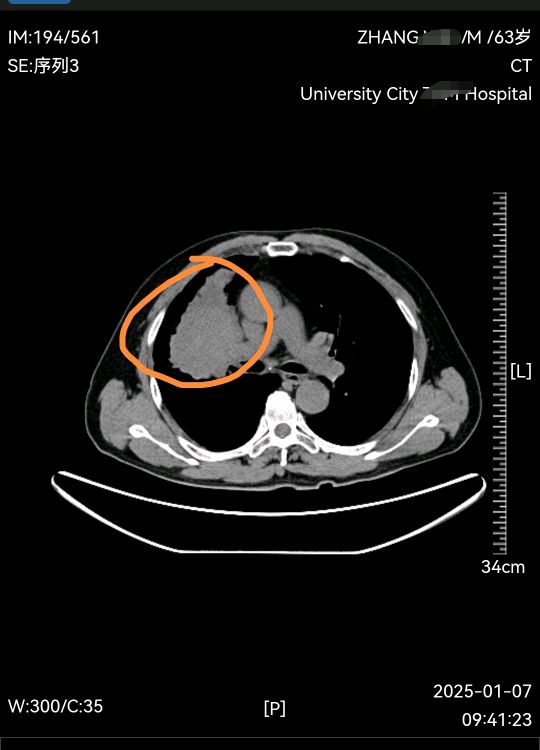

63岁老年男性患者,因为咳嗽伴有血丝痰在当地医院确诊右上肺鳞癌,肿瘤较大侵犯肺动脉暂没有手术机会,在当地医院化疗联合免疫治疗四个疗程后复查肿瘤明显缩小,患者和家属手术愿望强烈,来我门诊就诊复查PET后评估手术还是有机会,遂收入院完善术前检查,顺利完成右中上肺叶切除肺癌根治手术,手术过程顺利,切除彻底干净,术后继续免疫维持治疗,估计会取得不错的预后。